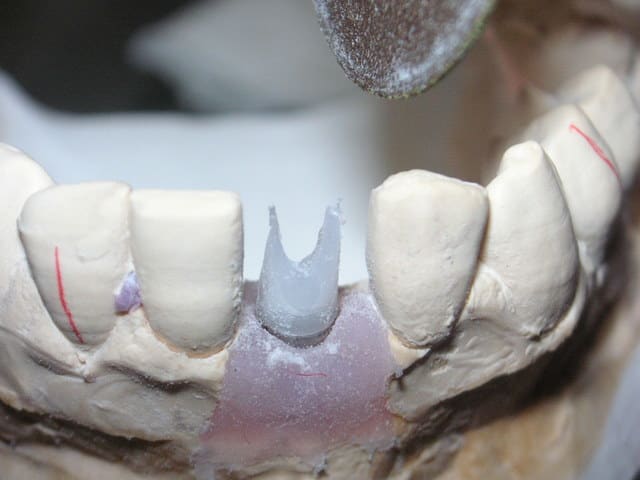

Pour remplacer 31 et 41:

Un Implant central de 3,75 ou 4,00 avec émergence de vis linguale.

Un pilier Zircone "Bifide" avec céramique montée directement dessus et fausse gencive céramique.

C'est simple, pérenne et très joli.